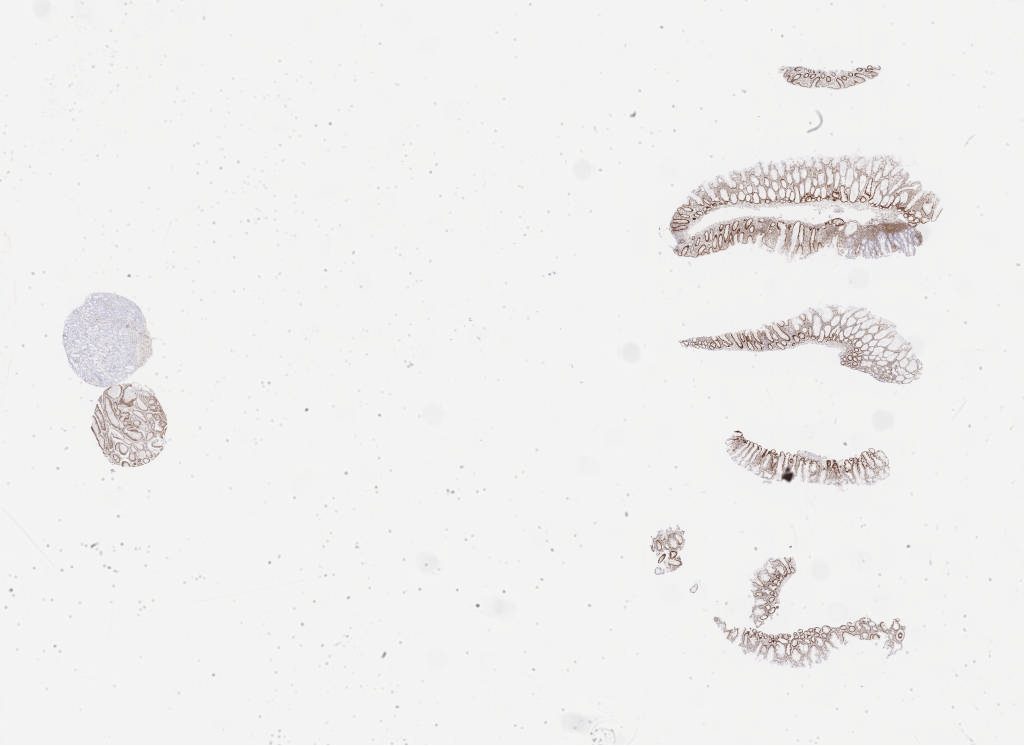

Case3 mlh 1a.svs

75696

x

55134

@

40X